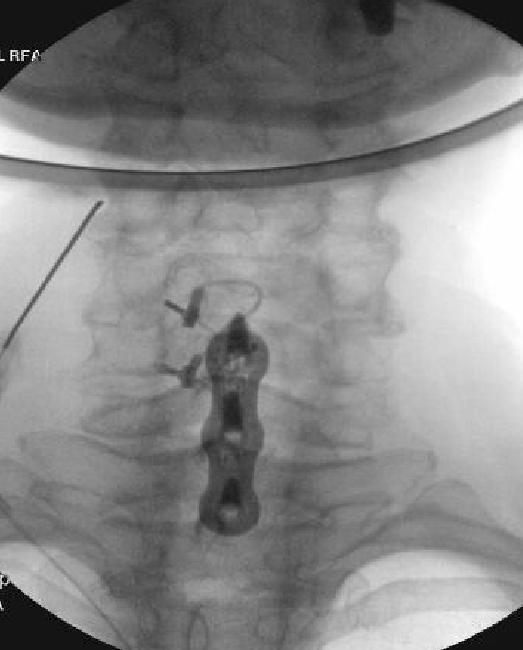

Nasty neuritis. This is 80 degrees 90 seconds.

These images look great. Sorry it happened? Steroid?

Lyrica Rx sent in, and we're starting it for chronic pain (and neuritis). She gets a shoulder scope in two weeks for a large RCT. I like antineuropathics (gabapentin 100mg HS or BID) perioperatively in general. I wish they were given 2 weeks before and after ALL orthopedic surgeries.

Dexamethasone given before RFA needles were removed.